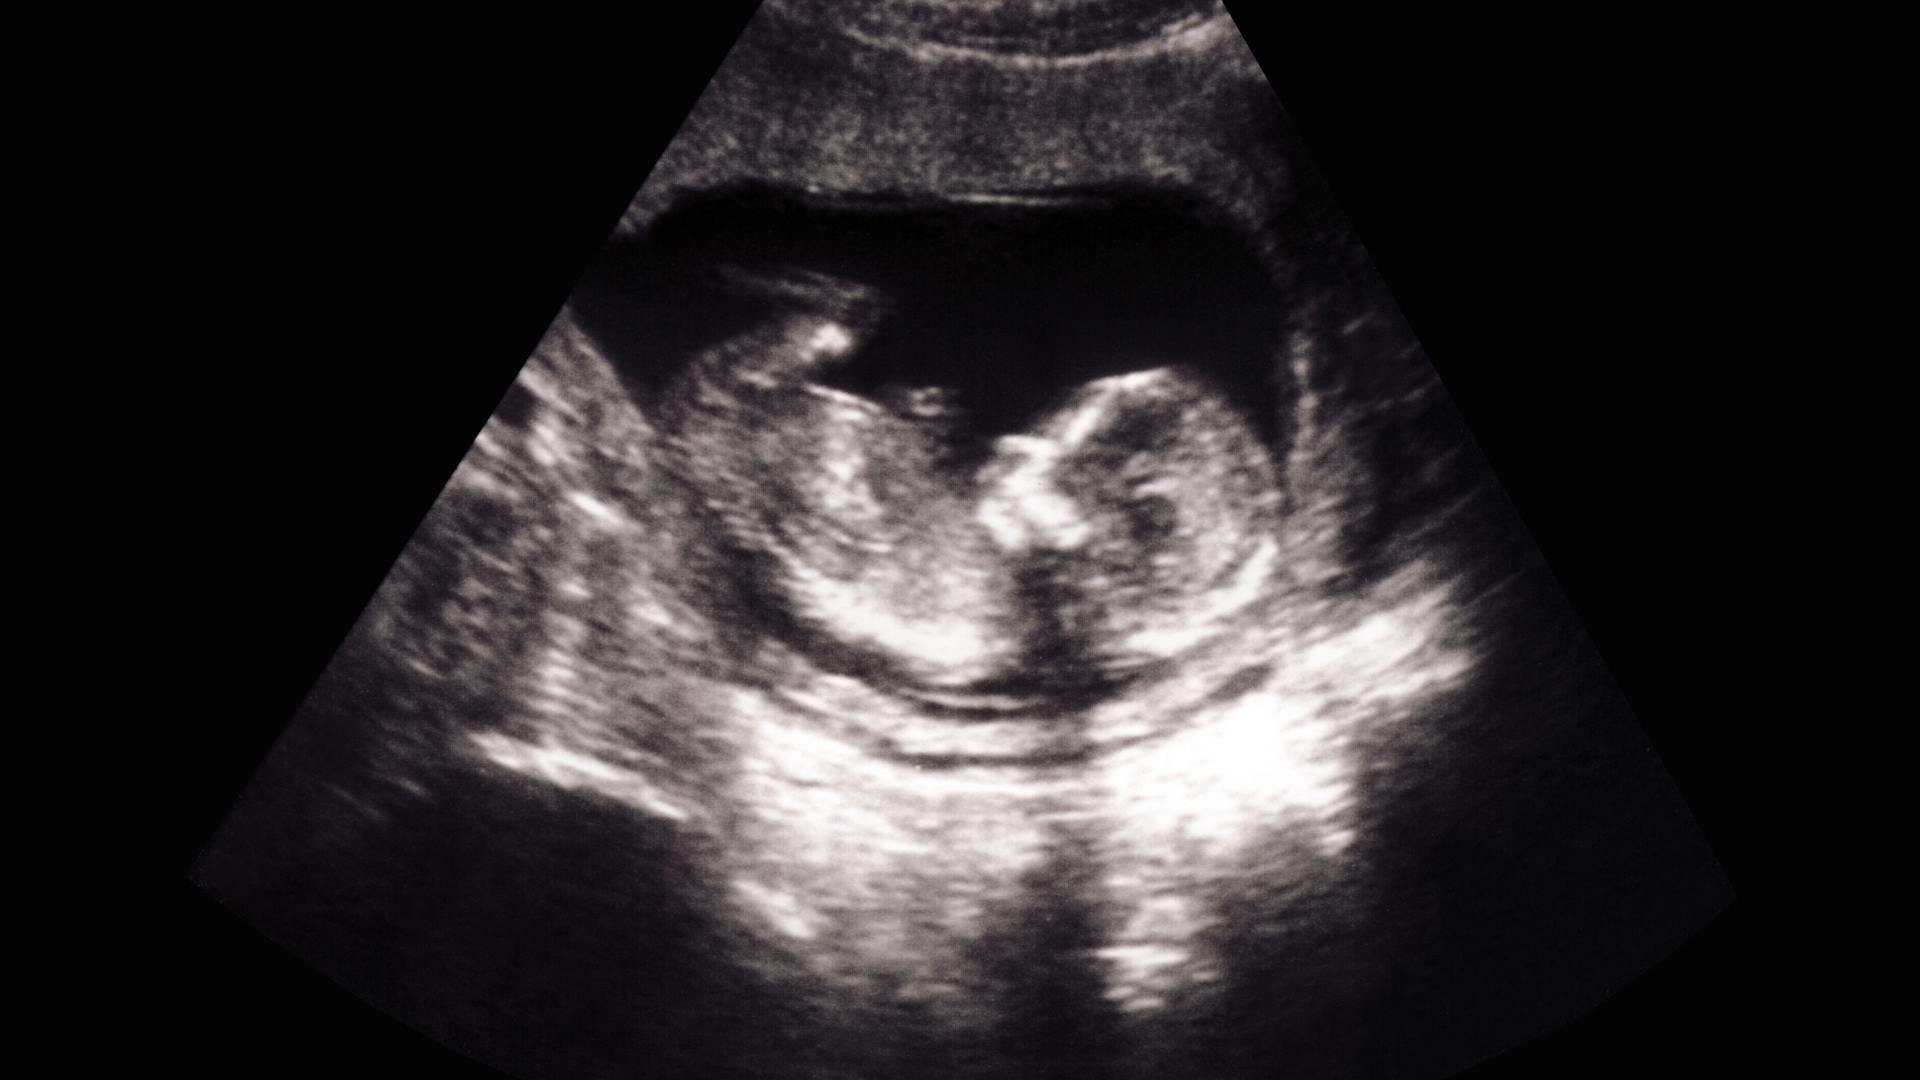

Siêu âm đúng lịch hẹn

Siêu âm là phương tiện chính xác giúp đánh giá toàn diện sức khỏe và vị trí của thai nhi trong bụng mẹ.

Đánh giá tăng trưởng thai: Siêu âm giúp kiểm tra cân nặng thai, chiều dài xương đùi và chu vi vòng đầu.

Kiểm tra lượng nước ối và bánh nhau: Siêu âm xác định vị trí bánh nhau, lượng nước ối và các dấu hiệu liên quan đến sức khỏe thai nhi.

Theo dõi vị trí thai: Thai quay đầu, thai ngôi mông hay thai nằm ngang đều được xác định qua siêu âm.